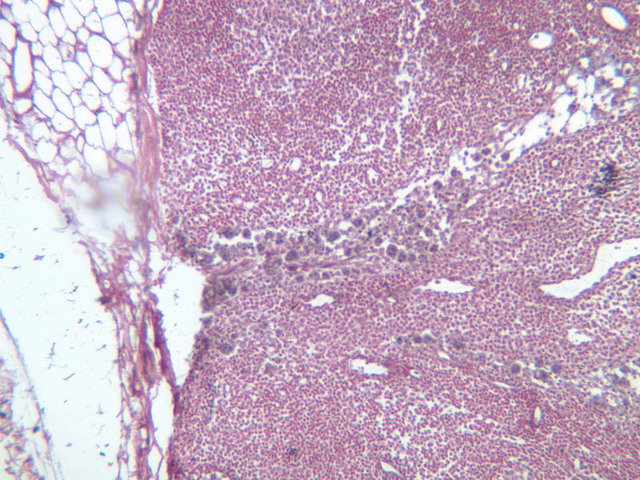

Another encapsulated lymphoid organ is the thymus. In the developing animal, this tissue contains the most important concentration of lymphocytes in the body. If the thymus is removed, lymphoid nodular tissue elsewhere does not develop properly and the ability of the animal to develop immunological competence is impaired. In a newborn or young animal, therefore, the thymus is a large lymphoid structure. After maturity the thymus undergoes involution, although some of the structural features persist and will be found embedded in fatty tissue.

Examine slides A-43 through A-46 (A-43, H&E [2.5x, 10x, 20x]; A-44, H&E [10x, 20x, 40x]; A-46, H&E [2.5x-labeled, 10x, 20x-labeled, 40x]). Slides A-44 and [[http://www.medicalhistology.us/wiki/bin/viewfile/Main/ThymusImages?rev=1;filename=a45_hassall_corpuscle_medulla_infant_thymus_2x.jpg][A- 45]] are from infants and slide A-46 is from a young adolescent. Compare slide A-43 (adult thymus) to slide A-44 (infant thymus). First hold the slides up to the light and observe by eye that there is an increase in the amount of CT (and fat) that infiltrates the tissue with age. Now observe the differences in the appearance of the tissue at the microscopic level. Like the lymph node and spleen, the thymus is encapsulated, and the capsular connective tissue penetrates into the lymphoid tissue dividing it into compartments. But only the thymus appears lobulated. Each lobule is divided into a darker staining peripheral cortex and a lighter staining medulla. Diagnostic of the thymus are Hassall's corpuscles (A-45 [2.5x, 10x, 20x, 40x-labeled]). These are concentrically layered, eosinophilic structures found in the medulla.

Examine a section of young thymus (slides A-44, A-45). Note that it is surrounded by a thin CT capsule. Trabeculae from the capsule pass into the organ to divide the thymus incompletely into lobes (separated by thick trabeculae) and lobules (separated by thinner trabeculae). Notice that the lobules and lobes join centrally, making the parenchyma of the organ continuous throughout. Each lobule shows an outer, cortical region, densely packed with cells that are mostly lymphocytes, and a core or medullary region containing fewer cells. Lymphoid nodules with their germinal centers are absent from the thymus because it has no afferent lymphatics, i.e. this organ does not filter lymph. Examine the cortex and find large and small lymphocytes (A-44, H&E [2.5x, 10x, 20x, 40x] [2.5x, 10x, 20x, 40x]; A-45, H&E [10x, 20x, 40x] [2.5x, 10x, 20x, 40x] [2.5x, 10x, 20x, 40x]). Look for mitotic figures in the thymic cortex; these are lymphoblasts. Also try to discern large cells with acidophilic cytoplasm and large nuclei interspersed among the lymphocytes. These are the epithelioreticular cells. Now look at the medullary region where lymphocytes are sparser (A-44, H&E [10x, 20x, 40x]; A-45, H&E [2.5x, 10x, 20x, 40x-labeled] [10x, 20x, 40x]). Epithelioreticular cells are more readily apparent. Unlike the reticular cells in other lymphatic organs which are of mesenchymal descent, these reticular cells arise from epithelium of the pharyngeal pouches. Like other epithelial cells, thymic reticular cells are joined by desmosomes. In the thymus, the epithelioreticular cells form a cellular reticulum that supports the thymocytes.

Scattered randomly in the medullary tissue are acidophilic structures whose cells are concentrically arranged around an amorphous core. These are the thymic or Hassall's corpuscles. Hassall's corpuscles vary in size and appearance and are comprised of degenerated reticular cells that contain keratohyalin granules and keratin. No known function has been assigned to them.